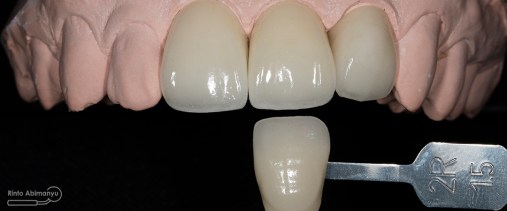

Saya lakukan pencocokan warna gigi pasien dengan shade guide dan meminta pasien juga memcocokan warna di giginya sehingga dicapai kesepakatan untuk menentukan warnanya..

Crown dari lab sudah jadi dan ketika saya coba cocokkan dengan shade guide hasilnya sangat memuaskan… Baik warna dan bentuk sesuai ekspektasi…..

Ketika dilakukan try in pada pasien pun tidak ada kendala… perfect fit…

Sementasi menggunakan semen resin Relyx Ultimate (3M) dan bonding Scotchbond Universal (3M) dilakukan isolasi maksimal daerah sekeliling gigi pada sementasi tersebut…